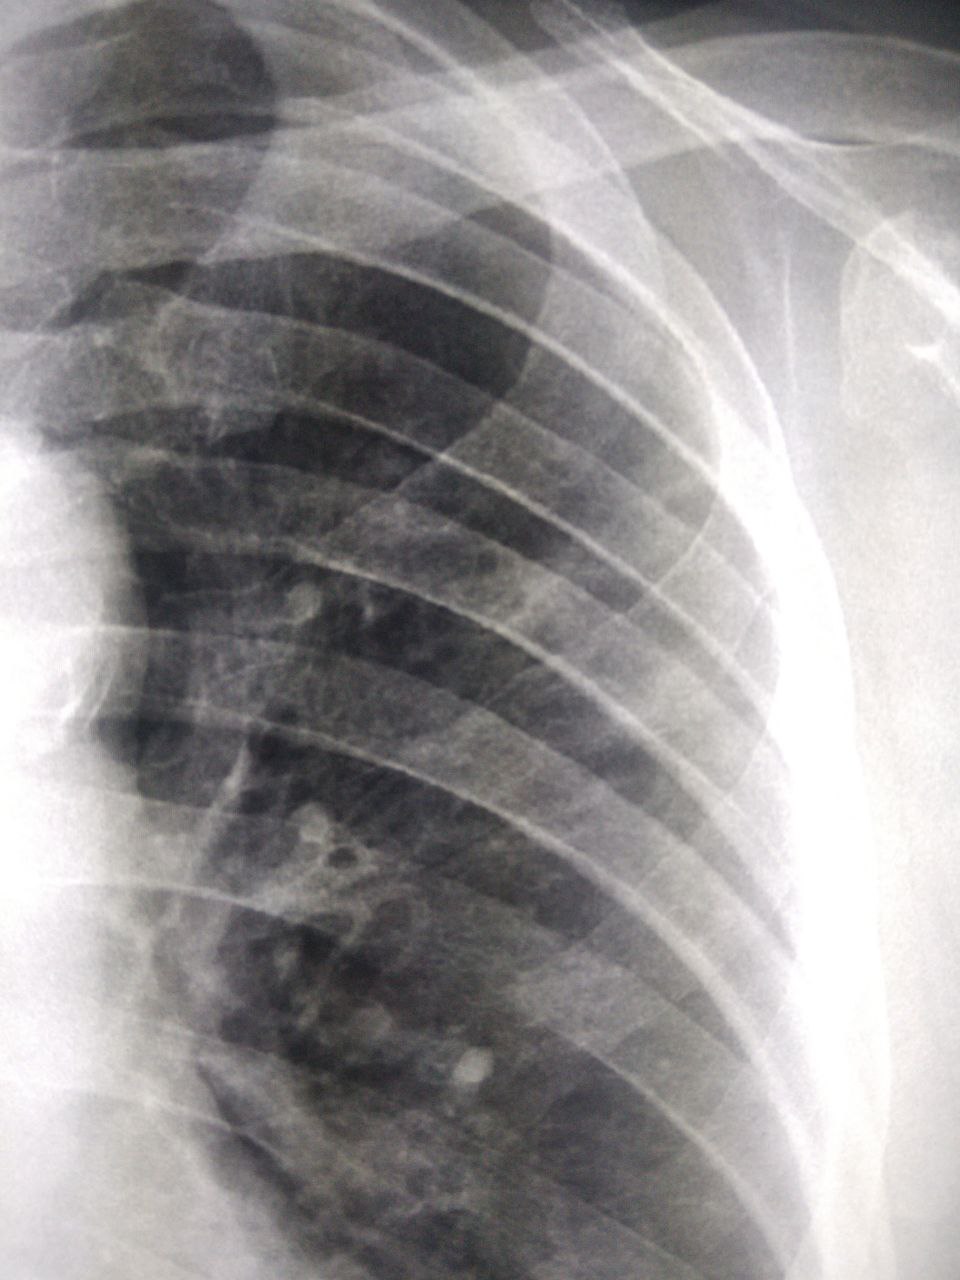

Александр in Radiology/Рентгенология Чатоид

С флг. Затемнения в 3 слева. В прошлом году не было. Проф.цель, т нет. Как можно интерпретировать?